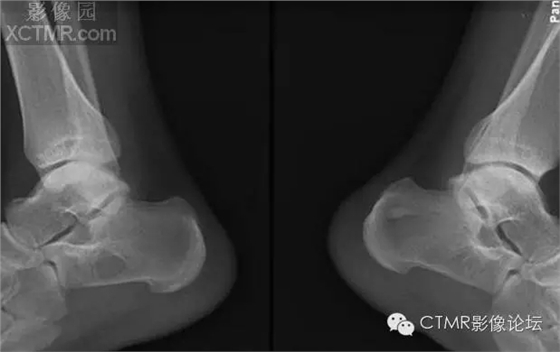

骨髓竇是指松質(zhì)骨內(nèi)先天性骨小梁發(fā)育稀少,各組骨小梁間的骨小梁少或缺如,形成一空腔,內(nèi)含有骨髓,稱為骨髓竇,為正常解剖變異。骨髓竇以跟骨最多見,簡稱骨髓竇,其次見于股骨頸、股骨遠(yuǎn)端及髖臼上緣等處。

【臨床表現(xiàn)】

成人多見,因系解剖變異,無癥狀。常因外傷或其他原因做X線檢查時發(fā)現(xiàn)。

【X線表現(xiàn)】

1.跟骨竇的形成 跟骨示足弓的重要支點(diǎn),承受著來自自身及負(fù)荷的重量。為了適應(yīng)承受重量的力學(xué)需要,跟骨的結(jié)構(gòu)十分精密合理。其骨小梁的發(fā)育有三組:①自跟距關(guān)節(jié)后緣向后下方呈斜向走行;②沿跟骨下方分布;③自跟結(jié)節(jié)處向前方伸展。三組骨小梁間有一個類三角形、圓形或橢圓形透亮區(qū),即跟骨竇。

2.跟骨竇的表現(xiàn) 觀察跟骨竇以側(cè)位平片為佳。其特點(diǎn)是位于跟骨前部中央,跟骨溝后方,尖端向上,足弓后上部,承受重量輕的特定位置。竇的基底與跟骨下緣平行。與竇基底相當(dāng)?shù)母窍戮壠べ|(zhì)密度高,呈致密帶狀或線狀。竇內(nèi)骨小梁稀少或缺如。邊緣清楚整齊,無硬化。大小1-3cm。竇內(nèi)有時可見營養(yǎng)溝。多數(shù)為單側(cè),少數(shù)雙側(cè)對稱發(fā)生。竇周骨質(zhì)正常。

【鑒別診斷】

1.跟骨囊腫 囊腫多位于跟骨后中部,與跟骨竇位置不同。呈圓形或橢圓形,囊內(nèi)無骨小梁,高度透亮,膨脹生長,周邊輕度硬化。

2.單房性巨細(xì)胞瘤 破壞區(qū)邊緣清楚,內(nèi)無骨間隔。骨皮質(zhì)變薄。臨床上有疼痛。腫瘤多位于跟骨后部,腫瘤中心多在跟骨竇之后。

3.跟骨結(jié)核 病變范圍較小,病變呈不規(guī)則破壞,邊緣模糊,無硬化,周圍骨質(zhì)疏松。

4. 骨內(nèi)脂肪瘤 骨內(nèi)脂肪瘤極罕見,多在長骨干骺。x光片見膨脹镕骨破壞,周邊光滑,有硬化緣,有時有鈣化灶,可誤診為骨梗死。病理:巨檢 黃色質(zhì)軟,脂肪祥,可鈣化或囊性變。

骨髓竇是指松質(zhì)骨內(nèi)先天性骨小梁發(fā)育稀少,各組骨小梁間的骨小梁少或缺如,形成一空腔,內(nèi)含有骨髓,稱為骨髓竇,為正常解剖變異。骨髓竇以跟骨最多見,簡稱骨髓竇,其次見于股骨頸、股骨遠(yuǎn)端及髖臼上緣等處。X線表現(xiàn)邊緣清楚整齊,無硬化,大小1-3cm,病變區(qū)內(nèi)無鈣化,竇內(nèi)有時可見營養(yǎng)溝。竇周骨質(zhì)正常。